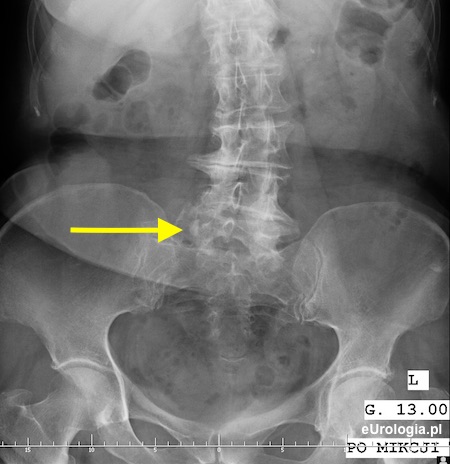

Kamica górnego odcinka moczowodu - urografia

Cień wapienny 11x8 mm na wysokosci wyrostka poprzecznego L5 po stronie prawej mogacy byc złogiem w górnym odcinku prawego moczowodu

Zółtą strzałką oznaczono cień wapienny o wymiarach 11x8 mm będący złogiem w górnym odcinku prawego moczowodu.